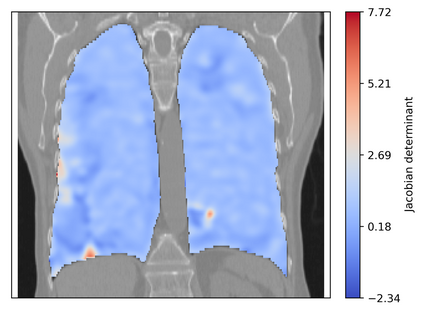

Deformable image registration is a fundamental task in medical image analysis and plays a crucial role in a wide range of clinical applications. Recently, deep learning-based approaches have been widely studied for deformable medical image registration and achieved promising results. However, existing deep learning image registration techniques do not theoretically guarantee topology-preserving transformations. This is a key property to preserve anatomical structures and achieve plausible transformations that can be used in real clinical settings. We propose a novel framework for deformable image registration. Firstly, we introduce a novel regulariser based on conformal-invariant properties in a nonlinear elasticity setting. Our regulariser enforces the deformation field to be smooth, invertible and orientation-preserving. More importantly, we strictly guarantee topology preservation yielding to a clinical meaningful registration. Secondly, we boost the performance of our regulariser through coordinate MLPs, where one can view the to-be-registered images as continuously differentiable entities. We demonstrate, through numerical and visual experiments, that our framework is able to outperform current techniques for image registration.